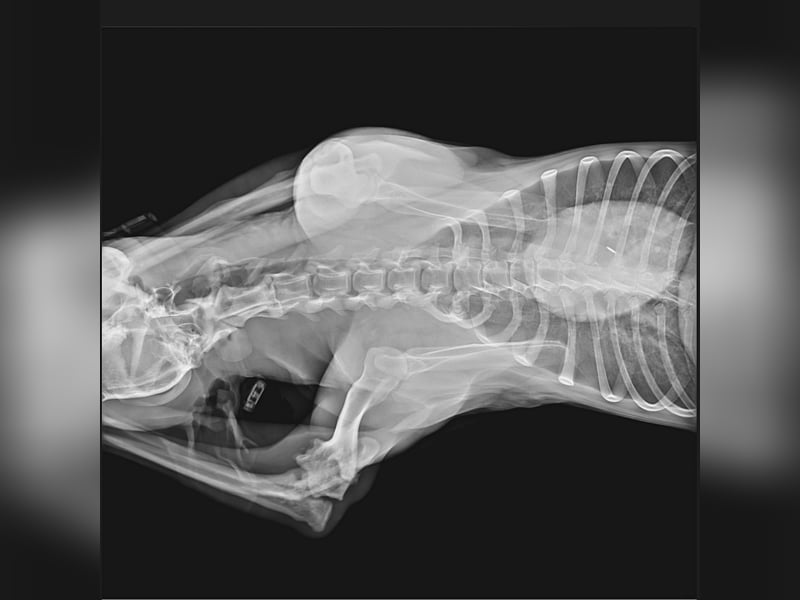

Einem unserer rumänischen Tierschützer fiel in der Tötung ein Hund auf, der am Bein verletzt zu sein schien. Dieser Hund lag sonst immer in einer Ecke, an diesem Tag sah er ihn zum ersten Mal in Bewegung - humpelnd. Wir wurden gebeten, ihn schnellstens herauszuholen, damit er einem Arzt vorgestellt werden konnte. ... der Arme tat uns so leid, aber erst einmal wollte man ihn nicht herausgeben, da angeblich seine Wartefrist noch nicht abgelaufen war. Als Druck gemacht wurde, durfte Miro - wie er nun genannt wird - diesen schrecklichen Ort dann doch verlassen. Wir haben Miro sofort röntgen lassen als er aus der Tötung geholt wurde. Der Tierarzt informierte uns, dass Miro eine Fraktur im Ellenbogen hat. Er muss schreckliche Schmerzen gehabt haben, das schlimme aber ist, dass diese Fraktur mittlerweile schon zu alt ist, sodass eine Operation nicht mehr in Frage kommt. Wie lange muss dieser arme Kerl mit schrecklichen Schmerzen ausgeharrt haben? Warum hat ihm niemand geholfen? Einen Arzt informiert? Dann hätte sein Bein behandelt werden können...

Wir haben die Röntgenbilder verschiedenen Ärzten gezeigt, die Antwort war dieselbe. Eine Operation ist aufgrund des Alters der Verletzung nicht mehr möglich, eine Versteifung des Gelenks nicht erforderlich, da er das Bein benutzt. Eine Bandage wird Miro zur Unterstützung ausreichen.